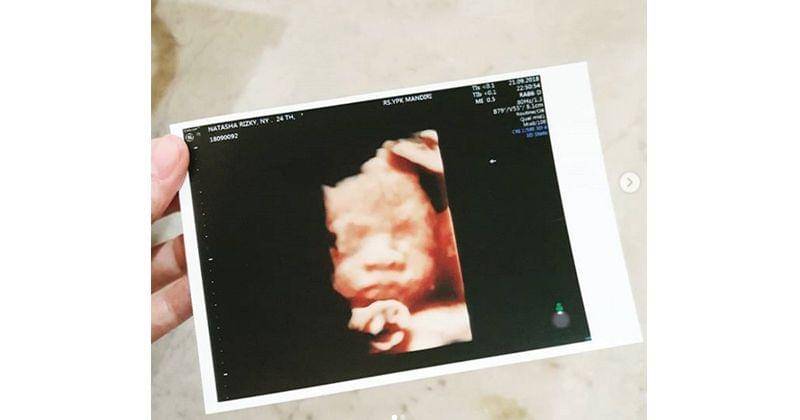

5. Sempat unggah foto USG

Beberapa waktu lalu Natasha sempat mengunggah foto ultrasonografi (USG) dari anak ketiganya. Desta pun pernah menyebut bahwa jenis kelamin anak ketiganya diperkirakan laki-laki.

Memiliki dua anak perempuan sebelumnya membuat Natasha dan Desta sangat bahagia jika benar kelak akan memiliki anak laki-laki.

Desta pun sempat mengunggah kabar ini di Instagram Story-nya. “Thank God. Finally, it's a boy,” tulis Desta.